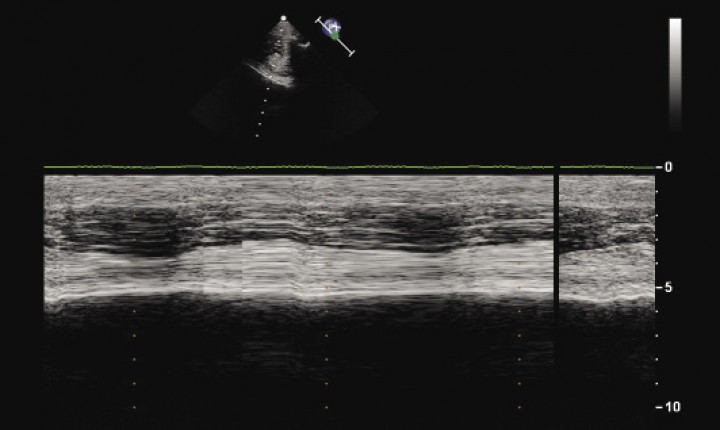

Considering the radiological findings, differential diagnoses at this point included dysfunction of the diaphragm (including paralysis and weakness), bilateral pleural adhesions, recurrent gastric dilation and, less likely, radiographs taken in expiration. Functional imaging with fluoroscopy, B-mode and M-mode ultrasonography of the diaphragm was planned to further evaluate diaphragmatic motion. Fluoroscopy revealed absence of diaphragm excursion during inspiration, and enhanced rib movement. Absence of movement of diaphragmatic crura was also detected upon M-mode ultrasonography (Fig. 3). These findings were consistent with bilateral diaphragmatic paralysis.

<p>M-mode ultrasonography image of the left hemidiaphragm for the dog in Figure 1 shows absence of diaphragmatic movement.</p>

M-mode ultrasonography image of the left hemidiaphragm for the dog in Figure 1 shows absence of diaphragmatic movement.